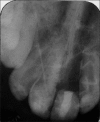

Extracted teeth can be bonded directly to adjacent teeth utilizing a prefabricated composite resin framework reinforced with polyethylene fiber as a noninvasive long-term provisional tooth replacement. This immediate provisional restoration allow for exact repositioning of the coronal part of the extracted tooth in its original intraoral three-dimensional position and thus relieves the apprehension of the patient caused by the sudden loss of an anterior tooth.